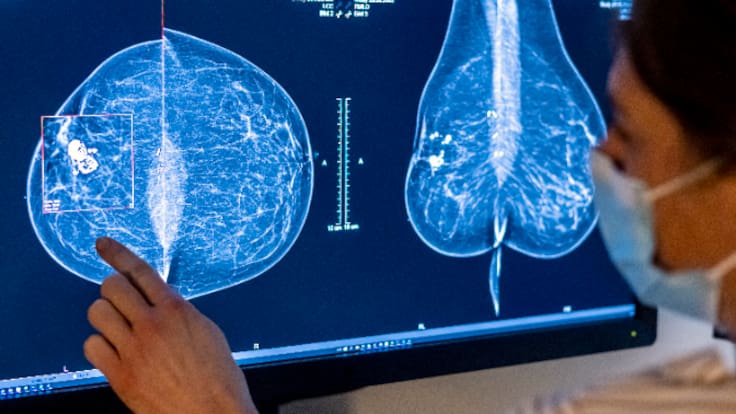

Las mujeres afectadas por los fallos en el programa de detección precoz del cáncer de mama vuelven movilizarse y expresar su impotencia e indignación, tras dar a conocer el presidente de la Junta en la presentación de su libro en Barcelona que algo más 23 mujeres han desarrollado cáncer de mama de las 2317 víctimas de los fallos en el cribado del cáncer de mama en Andalucía. Lamentan que, ahora tienen diagnóstico, con retraso, pero no saben cuándo las podrán operar, porque faltan quirófanos y faltan cirujanos.

Mujeres que, de nuevo, han denunciado su situación en la Cadena SER, como Chari, que relata cómo le han confirmado el diagnóstico de carcinoma infiltrante y "cuando escucho declaraciones como las de este señor siento ganas de vomitar. Es que le gritaría, le gritaría que es un mentiroso, además no ha solucionado nada, estoy en una lista de espera para operarme, me han dicho que la lista de espera es de unos dos meses, los cirujanos y los quirófanos hay los que hay, y todo esto sin saber todavía el alcance de mi lesión".

La SER vuelve a recoger los testimonios de estas víctimas del cribado de cáncer que se han enterado de su enfermedad meses o hasta dos años después de su primera mamografía por los retrasos desde el año 2021. Mujeres indignadas porque el presidente andaluz se haya ido a 1.000 kilómetros de Andalucía y, promocionando su libro ha deslizado el dato de las últimas víctimas de la negligencia, de las 2.317 contadas desde que la SER desveló el escándalo. Habló de ellas como un porcentaje aproximado, sobre un 1 por ciento, que son algo más de 23 personas.